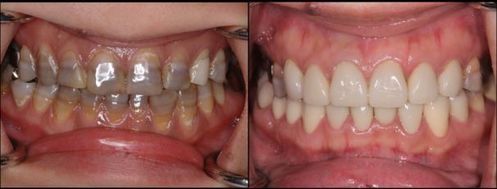

テトラサイクリンによる変色歯を

ラミネートべニアで審美回復した症例